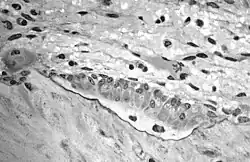

Aufnahme mehrerer Osteoblasten, den knochenaufbauenden Gegenspielern der Osteoklasten. In der TEM-Aufnahme ist das von den Osteoblasten synthetisierte Osteoid als helle, zur mineralisierten Knochenmatrix hin scharf abgegrenzten Zone (schwarze Grenzlinie) mit zwei eingelagerten Osteozyten (ehemalige Osteoblasten) gut zu erkennen.

Aufnahme mehrerer Osteoblasten, den knochenaufbauenden Gegenspielern der Osteoklasten. In der TEM-Aufnahme ist das von den Osteoblasten synthetisierte Osteoid als helle, zur mineralisierten Knochenmatrix hin scharf abgegrenzten Zone (schwarze Grenzlinie) mit zwei eingelagerten Osteozyten (ehemalige Osteoblasten) gut zu erkennen.